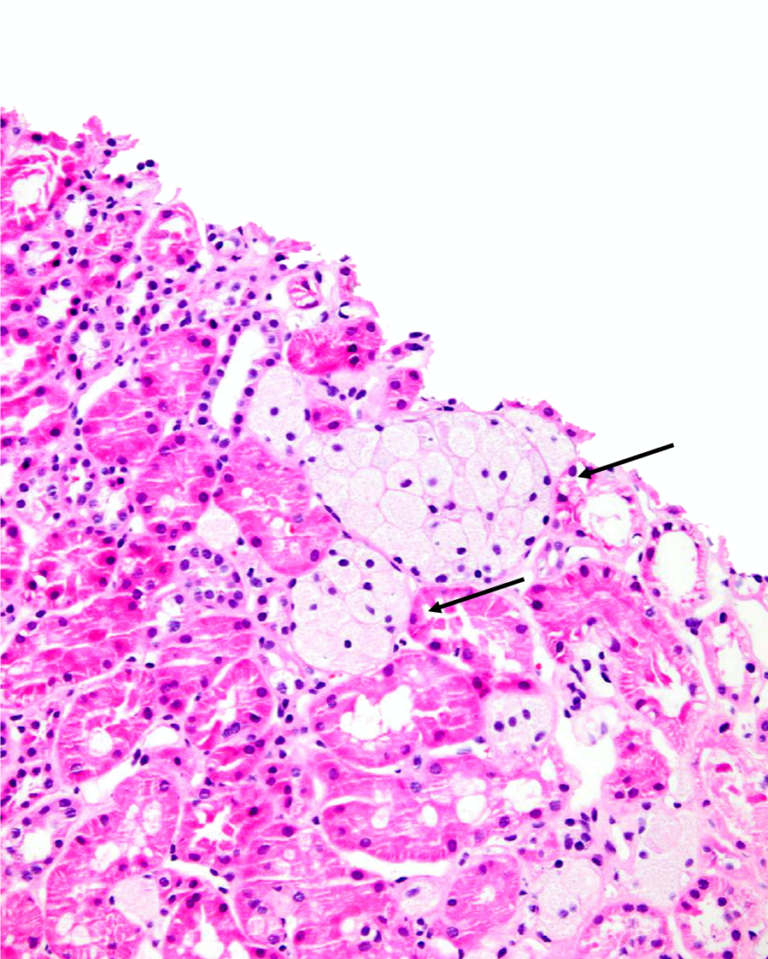

Foam cells are present in the papillary dermis (H and E X 400 Foam Cells Development This review aims to summarize the novel. Foam cells play a vital role in the initiation and development of atherosclerosis. The process of foam cell formation involves the expression of specific chemokine receptors and chemoattractant proteins (red). However, the mechanism that regulates the formation of macrophage. Foam cells are a type of macrophage that localize to fatty deposits on blood. Foam Cells Development.